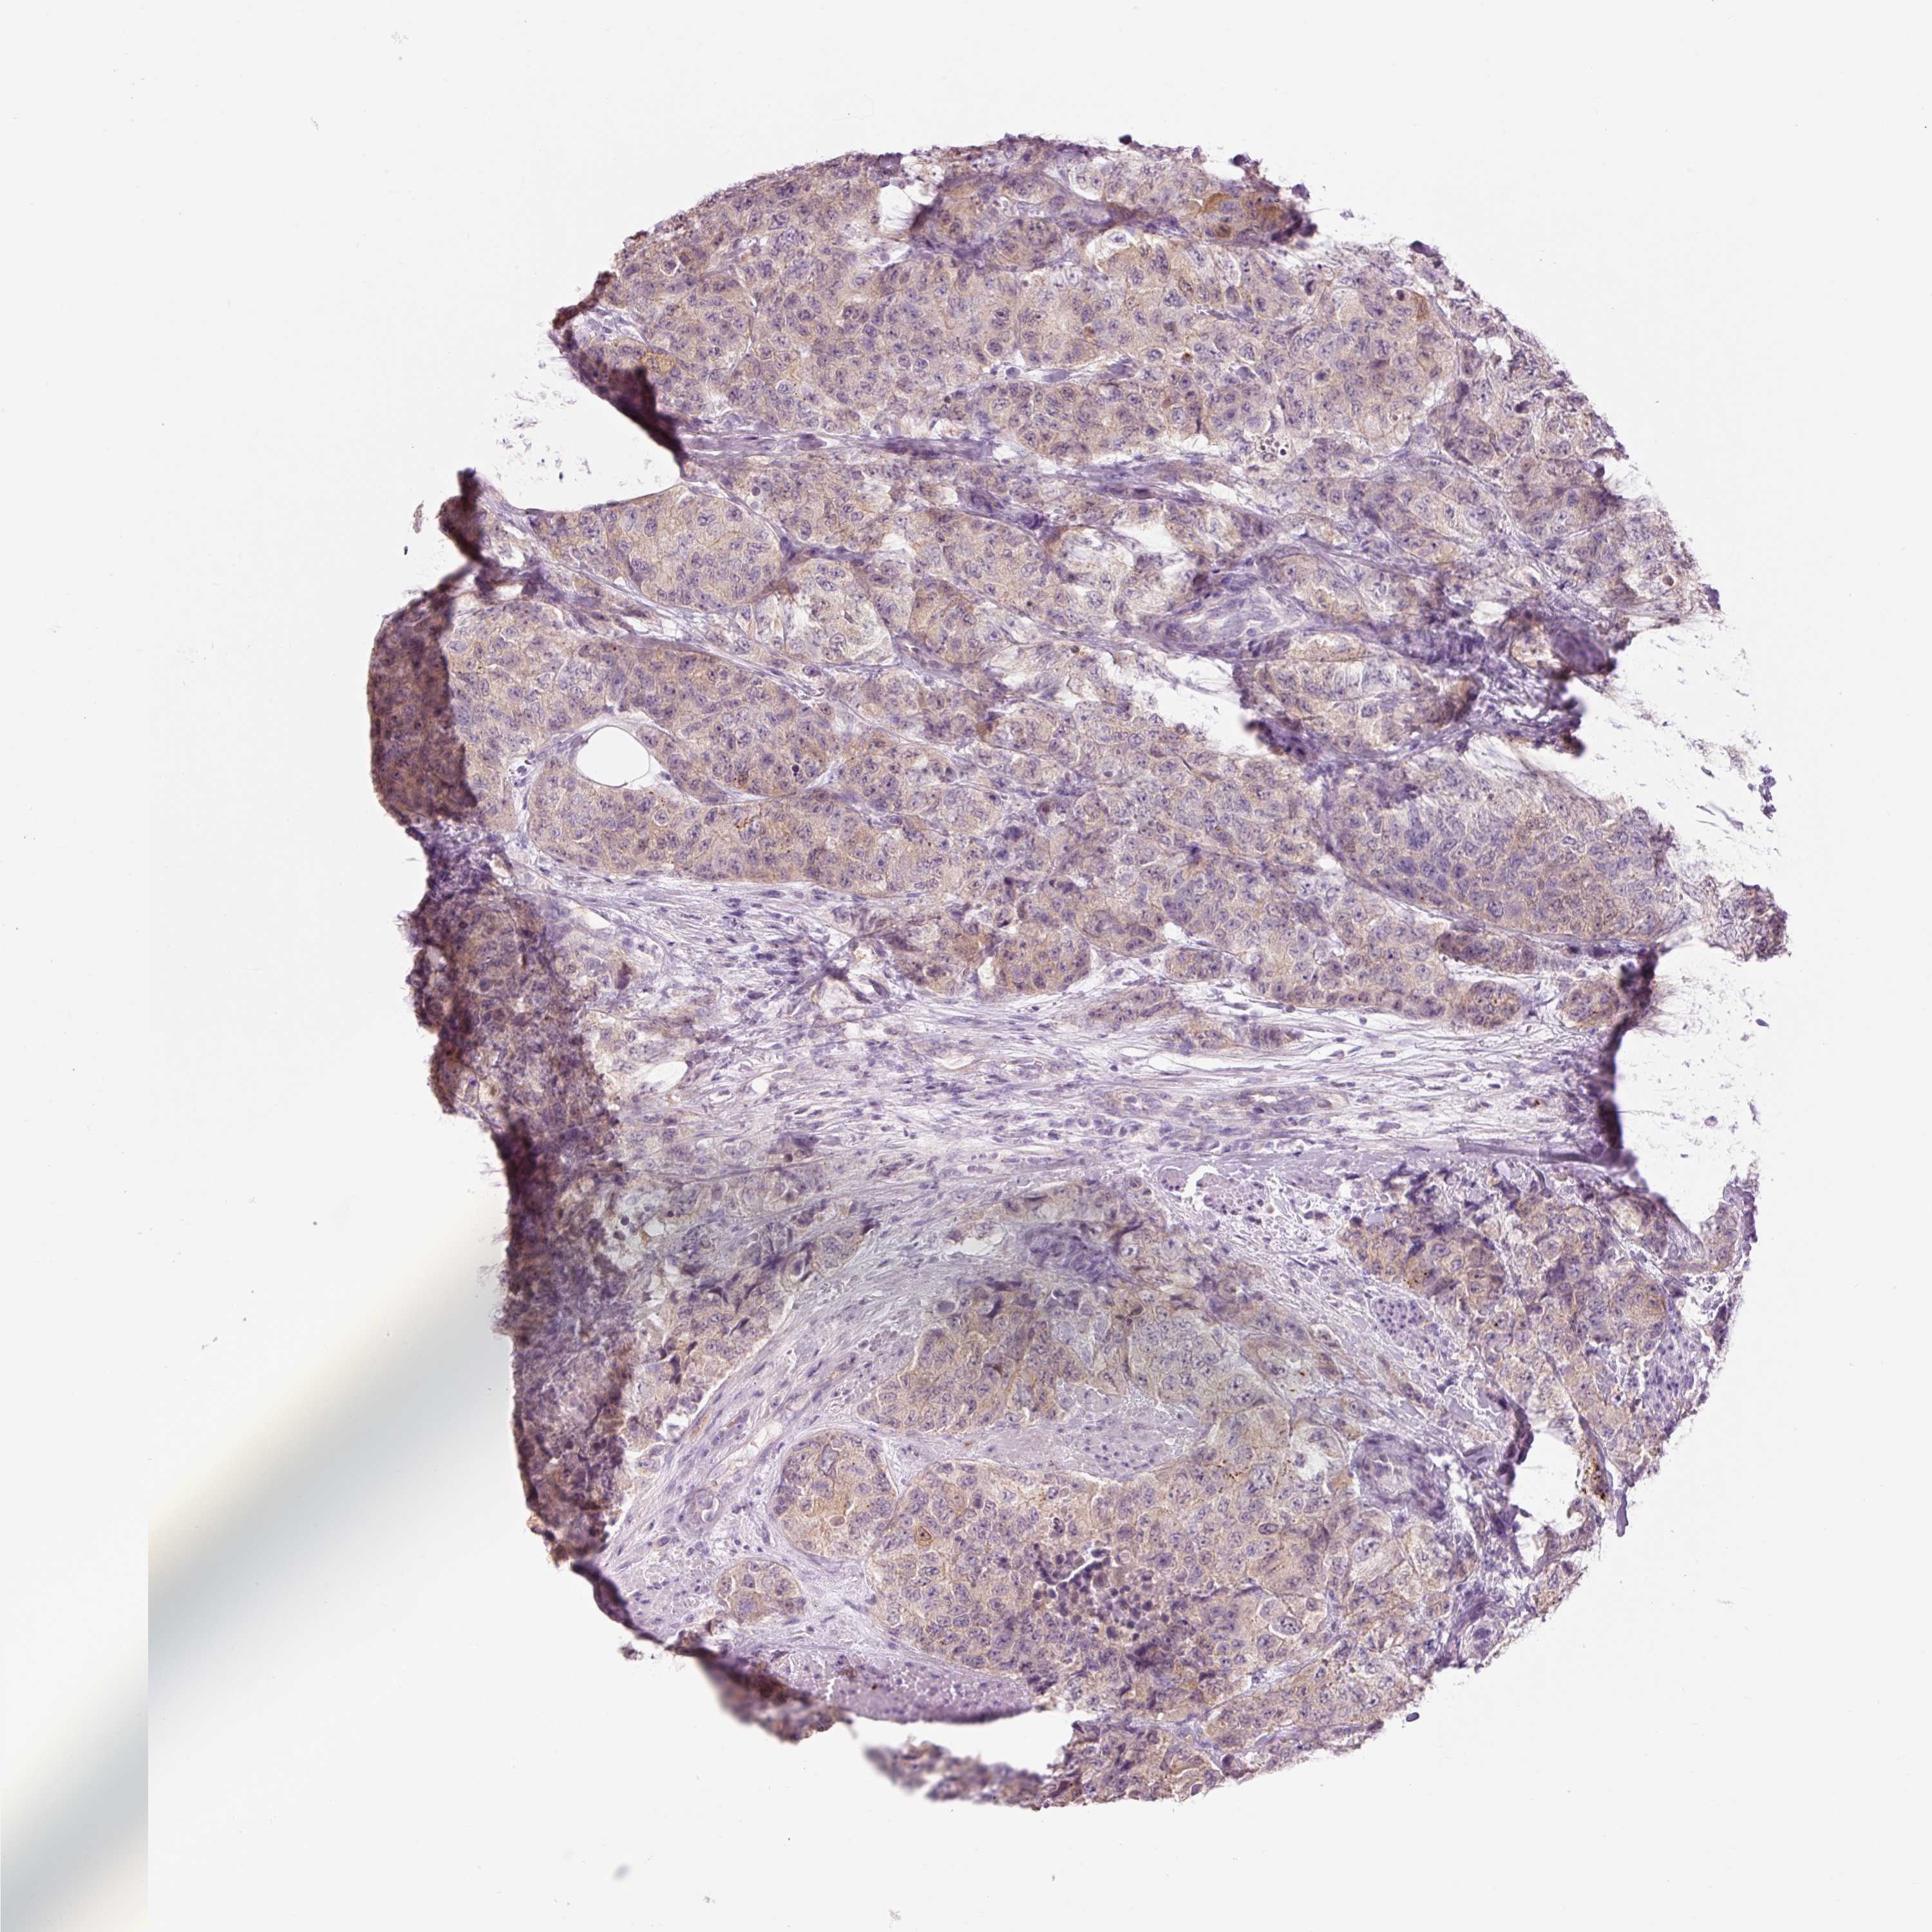

UROTHELIAL CANCER - Protein expressioni

A mouse-over function shows sample information and annotation data. Click on an image to view it in a full screen mode. Samples can be filtered based on level of antibody staining by selecting one or several of the following categories: high, medium, low and not detected. The assay and annotation is described here.

Antibody stainingi

Antibody staining in the annotated cell types in the current human tissue is reported as not detected, low, medium, or high, based on conventional immunohistochemistry profiling in selected tissues. This score is based on the combination of the staining intensity and fraction of stained cells.

Each image is clickable and will lead to virtual microscopy that enables deeper exploration of all samples and also displays staining intensity scores, fraction scores and subcellular localization as well as patient and tissue information for each sample.

Antibody HPA061446

Urothelial carcinoma, High grade

Urothelial carcinoma, NOS

Urothelial carcinoma, Low grade